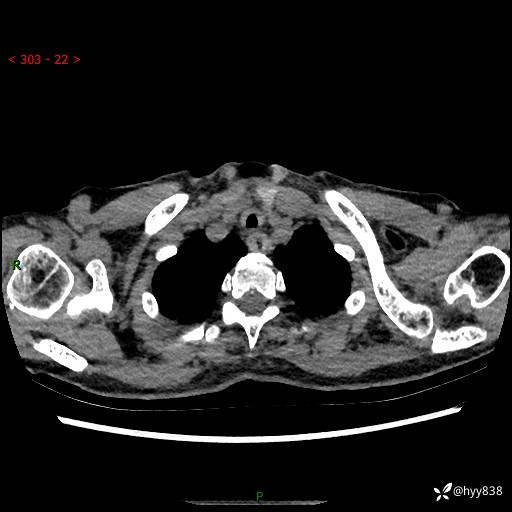

胸部CT平扫+增强